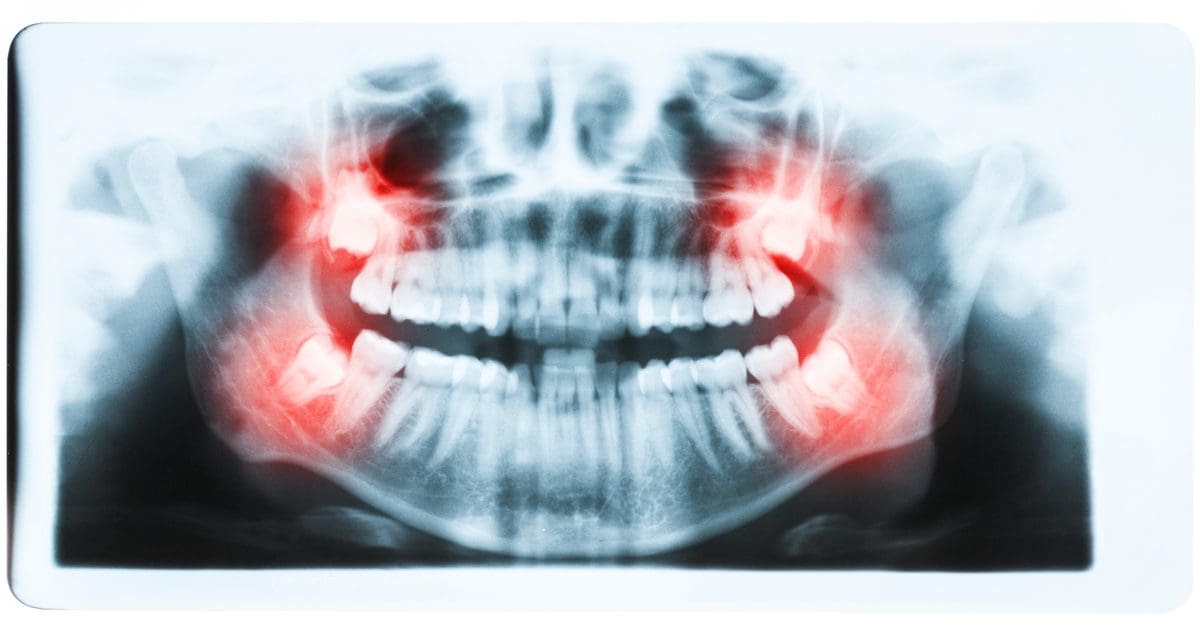

When wisdom teeth can’t erupt naturally, they become impacted. What is an impacted wisdom tooth? What are some treatments for impacted teeth? Here is some information for you.

One reason wisdom teeth can create such a problem is that they come in late. Wisdom teeth can erupt — or come in — crooked. They may also only come in partially. Wisdom teeth are notorious for erupting only halfway. They erupt either right at the gum line or halfway above the gumline. When this happens, the tooth becomes impacted.

Wisdom teeth can erupt partially out of your gumline. A partially impacted tooth means you are at risk for infection and tooth decay. When a tooth only partially erupts, it’s difficult to clean. Because bacteria are always present in your mouth, impacted teeth are more susceptible to infection. Both tooth decay and gum infections are hazardous to your dental health.